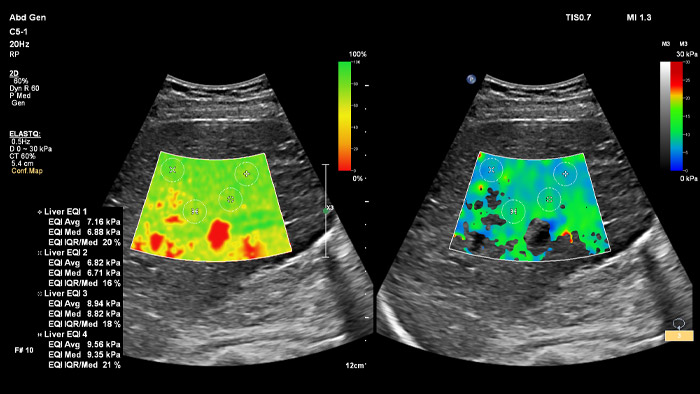

ElastQ Imagingを使用*。

*独自のConfidence MapとStiffness Mapを並列表示することでワークフローの手順を減らし、データ取得および計測の段階で関連付けて計測することができます。

ElastQは非侵襲的で再現性があり、簡単に実行でき、組織の硬さを2D Shear Wave(2D-SWE)でリアルタイムで評価します。ElastQでは保存した画像を使用して検査終了後にも計測することができ、Shear Waveが適切に伝搬されていることを示すConfidence Mapも含まれています。